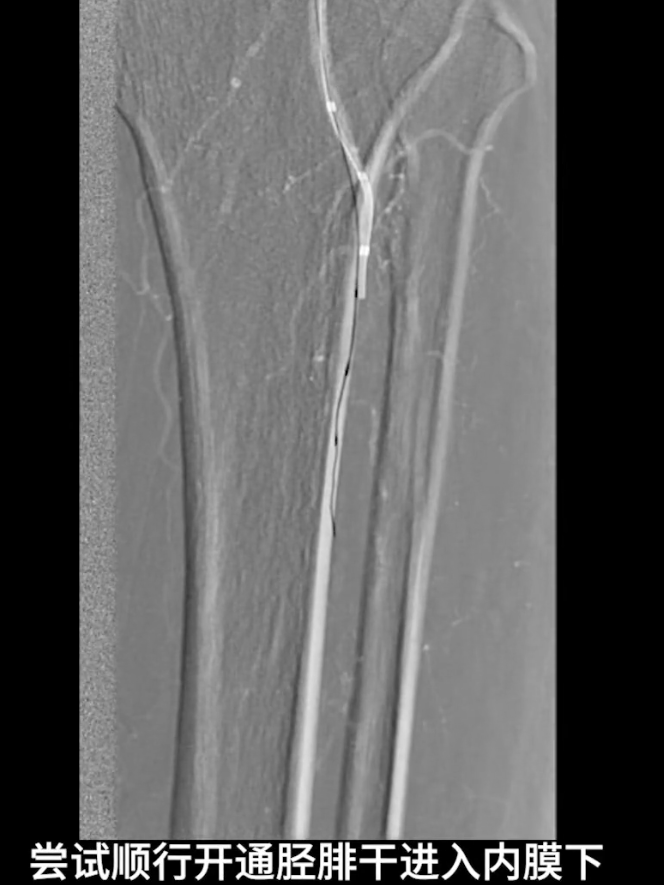

顺行开通尝试:以V18导丝配合支撑导管顺行开通胫腓干,导丝进入内膜下,开通受阻。